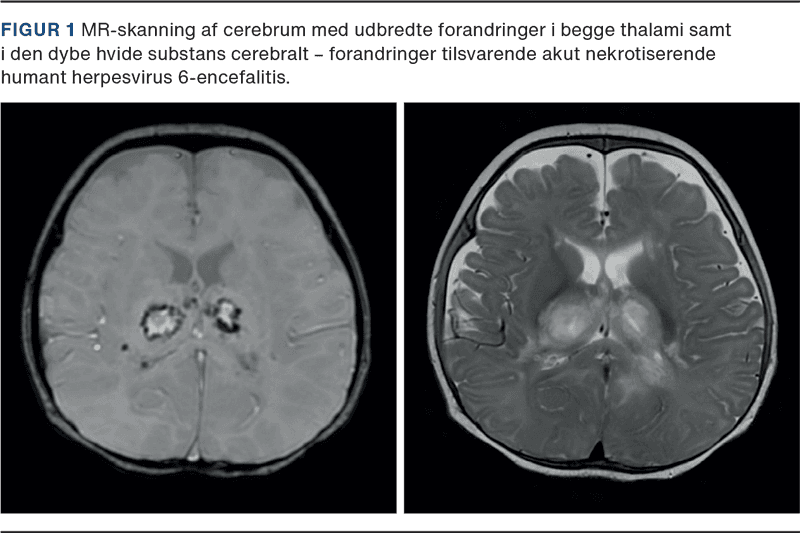

Barnet blev behandlet med fortsat mekanisk ventilation, betydelig kredsløbsstøtte, plasmaferese og hæmodialyse. MR-skanning af cerebrum viste udbredte forandringer i begge thalami samt i den dybe hvide substans svarende til HHV6-associeret ANE (Figur 1). På baggrund af det alvorlige neurologiske og hepatologiske sygdomsbillede og i samråd med forældrene blev der truffet beslutning om ikke at fortsætte med livsforlængende behandling. Barnet overgik til palliativ behandling og afgik ved døden efter en uges indlæggelse.